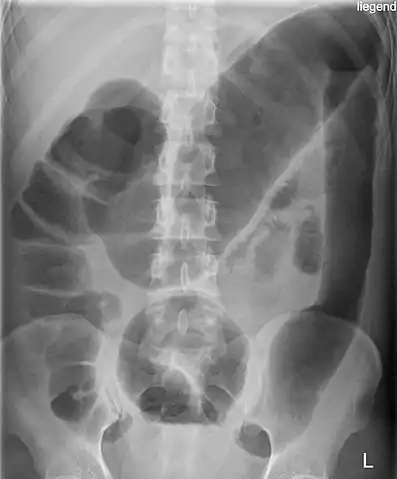

Abdominal X-ray with the features of Air-fluid level can be shown or CT Scan with Contrast can be done if the patient is stable.

Toxic megacolon in a patient with ulcerative colitis: The patient subsequently underwent a colectomy.